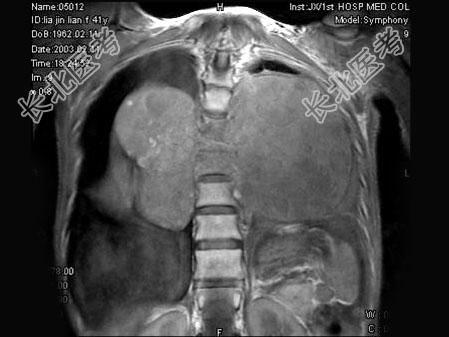

- 单项选择题女,41岁, 胸背部疼痛,肢体活动感觉障碍2年余, MRI检查见T

、T

椎体及附件骨质破坏,并向周围形成巨大肿块影, 呈T1低信号为主,T2加权有多个大小不一圆形混杂高信号, 边界清楚,最可能的诊断是 ( )